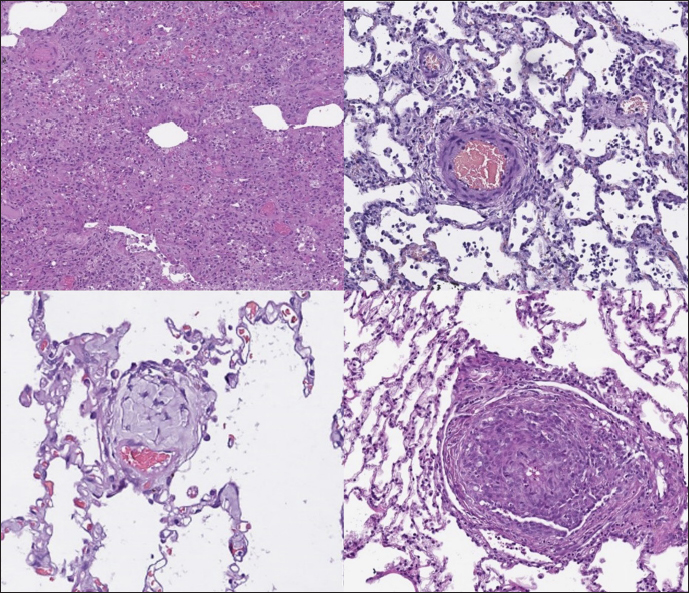

In dogs with RHF, with both Masson’s trichrome and hematoxylin and eosin staining, we found wide fields of pulmonary fibrosis, arterial thickening due to tunica media proliferation, and plexiform vascular lesions with signs of revascularization. The dog with pneumonitis showed chronic interstitial histiocytic pneumonia (Fig. 3).

In the sPCH group, we found zones of multifocal mild-to-moderate alveolar septa thickening with numerous capillary proliferation with signs of congestion. Endothelial cells were flattened, but had no signs of anisocytosis or anisokariosis. The growing capillaries expanded in pulmonary tissue, forming nodules and web-like anastomosis with bizarre vessel proliferation which affects zonal bronchi and arteriolas (Figs. 4 and 5).

Immunohistochemical labeling with anti-CD31 antibody and anti-factor von Willebrand antibody showed wide dispersion between the groups. In the RHF group, we found a weak-to-absent reaction for the CD31 marker in most of the fibrotic fields, restricted to endothelial cells. Additionally, we discovered an intensive reaction to von Willebrand factor in most arterioles and in vessels with plexiform morphology. In sPCH animals, we observed significant expression of CD31 marker covering most of the fields and actively present in alveolar septae with numerous capillaries. However, the representation of von Willebrand factor was almost absent (Figs. 6 and 7).

Fig. 3. RHF group. Left top—aggressive lung remodeling, resembling organizing diffuse alveolar damage with collapse and fusion of the alveoli and loss of typical structure. Right top—tunica media and adventitia proliferation around pulmonary vessel. Left bottom—partial occlusion of pulmonary vessel. Right bottom—plexiform vasculopathy with lumen obstruction and revascularization, presented with onion-like structure. Stained with H&E.

Fig. 4. sPCH group. Left (dog)—portions of alveolar septae with duplicated capillaries and capillaries proliferation into arterial walls. Right (cat)—less prominent septal alteration, significant arterial walls capillary proliferation. Stained with H&E.